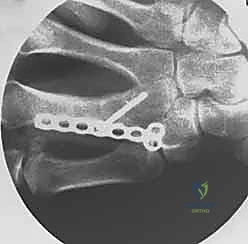

خطوات التثبيت الجراحي - توثيق بصري (Intraoperative Imaging)

يحرص الدكتور هطيف على توثيق خطوات العمل الجراحي لضمان أعلى مستويات الدقة. نستعرض هنا مجموعة من الصور من داخل غرفة العمليات توضح مدى تعقيد ودقة هذه الجراحات:

تتطلب الجراحة انتباهاً خاصاً للأوتار الباسطة والقابضة والأعصاب الدقيقة المحيطة بالعظام. استخدام تقنيات الجراحة الميكروسكوبية (Microsurgery) يضمن عدم الإضرار بهذه الأنسجة الحساسة.

معرض الصور الشعاعية: تقييم النتائج الجراحية (Post-Op X-rays)

النجاح الحقيقي يُقاس بالاستعادة المثالية للشكل التشريحي للعظم. توضح هذه الصور الشعاعية بعد الجراحة الدقة المتناهية في إعادة محاذاة العظام وتثبيتها.

التثبيت المحكم يسمح بالشفاء العظمي الأولي (Primary Bone Healing) دون تكوين كتلة عظمية كبيرة (Callus) قد تعيق حركة الأوتار المنزلقة فوقها.